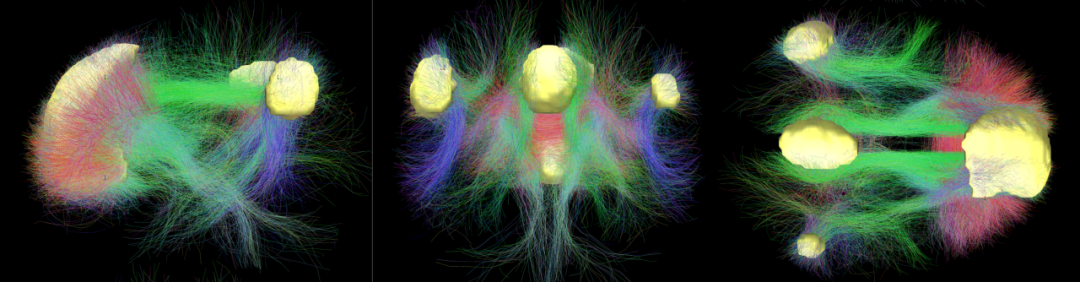

默认模式网络(default mode network)活动的降低是大脑在集中注意力时最明显的信号。默认神经网络主要由内侧前额叶皮质,后扣带回皮质和角形脑回(angular gyrus)组成,是一个横跨整个大脑的大型神经网络。在人们无事可做、胡思乱想的时候,默认神经网络会变得非常活跃。同时,它也参与包括环境观测、自我参照、社会认知等其他复杂的认知功能。

大脑默认模式网络的 3D 模拟图像

Andreashorn